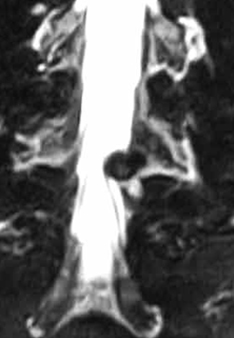

MRI可准确评价脊柱和各种病理情况。查看椎间盘病变・把握神经走向状态,精确诊断椎间盘突出,椎管狭窄等症的必要检查。 |

MRI图像